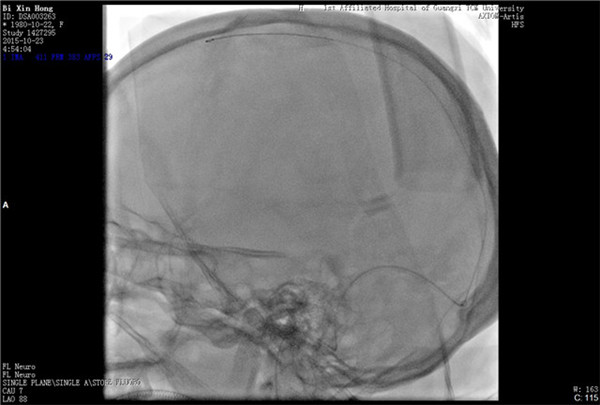

经与患者及家属充分沟通并获得同意后,外六科脑血管病介入治疗团队立即为患者行全脑血管造影,造影结果证实上矢状窦血栓形成,整个上矢状窦完全闭塞,若不采取措施病情很快就会恶化。再次征得家属同意后果断采取微导管介入手术治疗,手术在起病后当晚开始,由于患者血栓位置深在,需要经动、静脉双重途径置管,技术难度较大。术者选取Solitaire支架( 美国 公司)置入微导管远端,释放支架并在原位作短暂停留使支架与血栓充分接触并黏附,一起回撤支架与微导管取出血栓,手术一直持续到第二天凌晨。术后留置导管一条,用于每天以药物继续溶栓。术后患者即清醒,头痛明显缓解,无神经功能缺失。手术第二周时患者已经能够生活自理。2015年12月12日患者痊愈出院。

支架取出血栓

术后上矢状窦恢复通畅